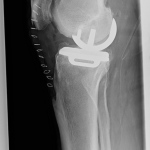

PRACHATICE – Na ortopedickém oddělení Nemocnice Prachatice byl minulý týden proveden unikátní výkon – implantace oboustranné částečné náhrady kolenního kloubu. Jde o málo frekventovaný typ operace, který se provádí jen na menším počtu ortoepedických pracovišť v České republice.

Unikondylární náhrada představuje šetrnější variantu totální endoprotézy – nahrazuje pouze poškozenou část kolenního kloubu, zatímco zbytek zůstává zachován. Aby pacient z operace skutečně profitoval, je nutné splnění indikačních kritérií, která lze shrnout do několika bodů: artrotické postižení jedné poloviny kloubu a dobrý stav té druhé, funkční vazy, dobrý rozsah pohybu, nepřítomnost výrazné deformity.

S oboustrannými implantacemi totálních endoprotéz mají v prachatické nemocnici již několikaleté zkušenosti. Nyní však poprvé provedli dvojitou operaci částečné náhrady. Zásadní je přitom nejen zvládnutá operační technika, ale i souhra celého týmu, díky které je pacient schopen se již v prvních hodinách po výkonu postavit, operované klouby zatížit a relativně bezbolestně zvládat rehabilitaci.